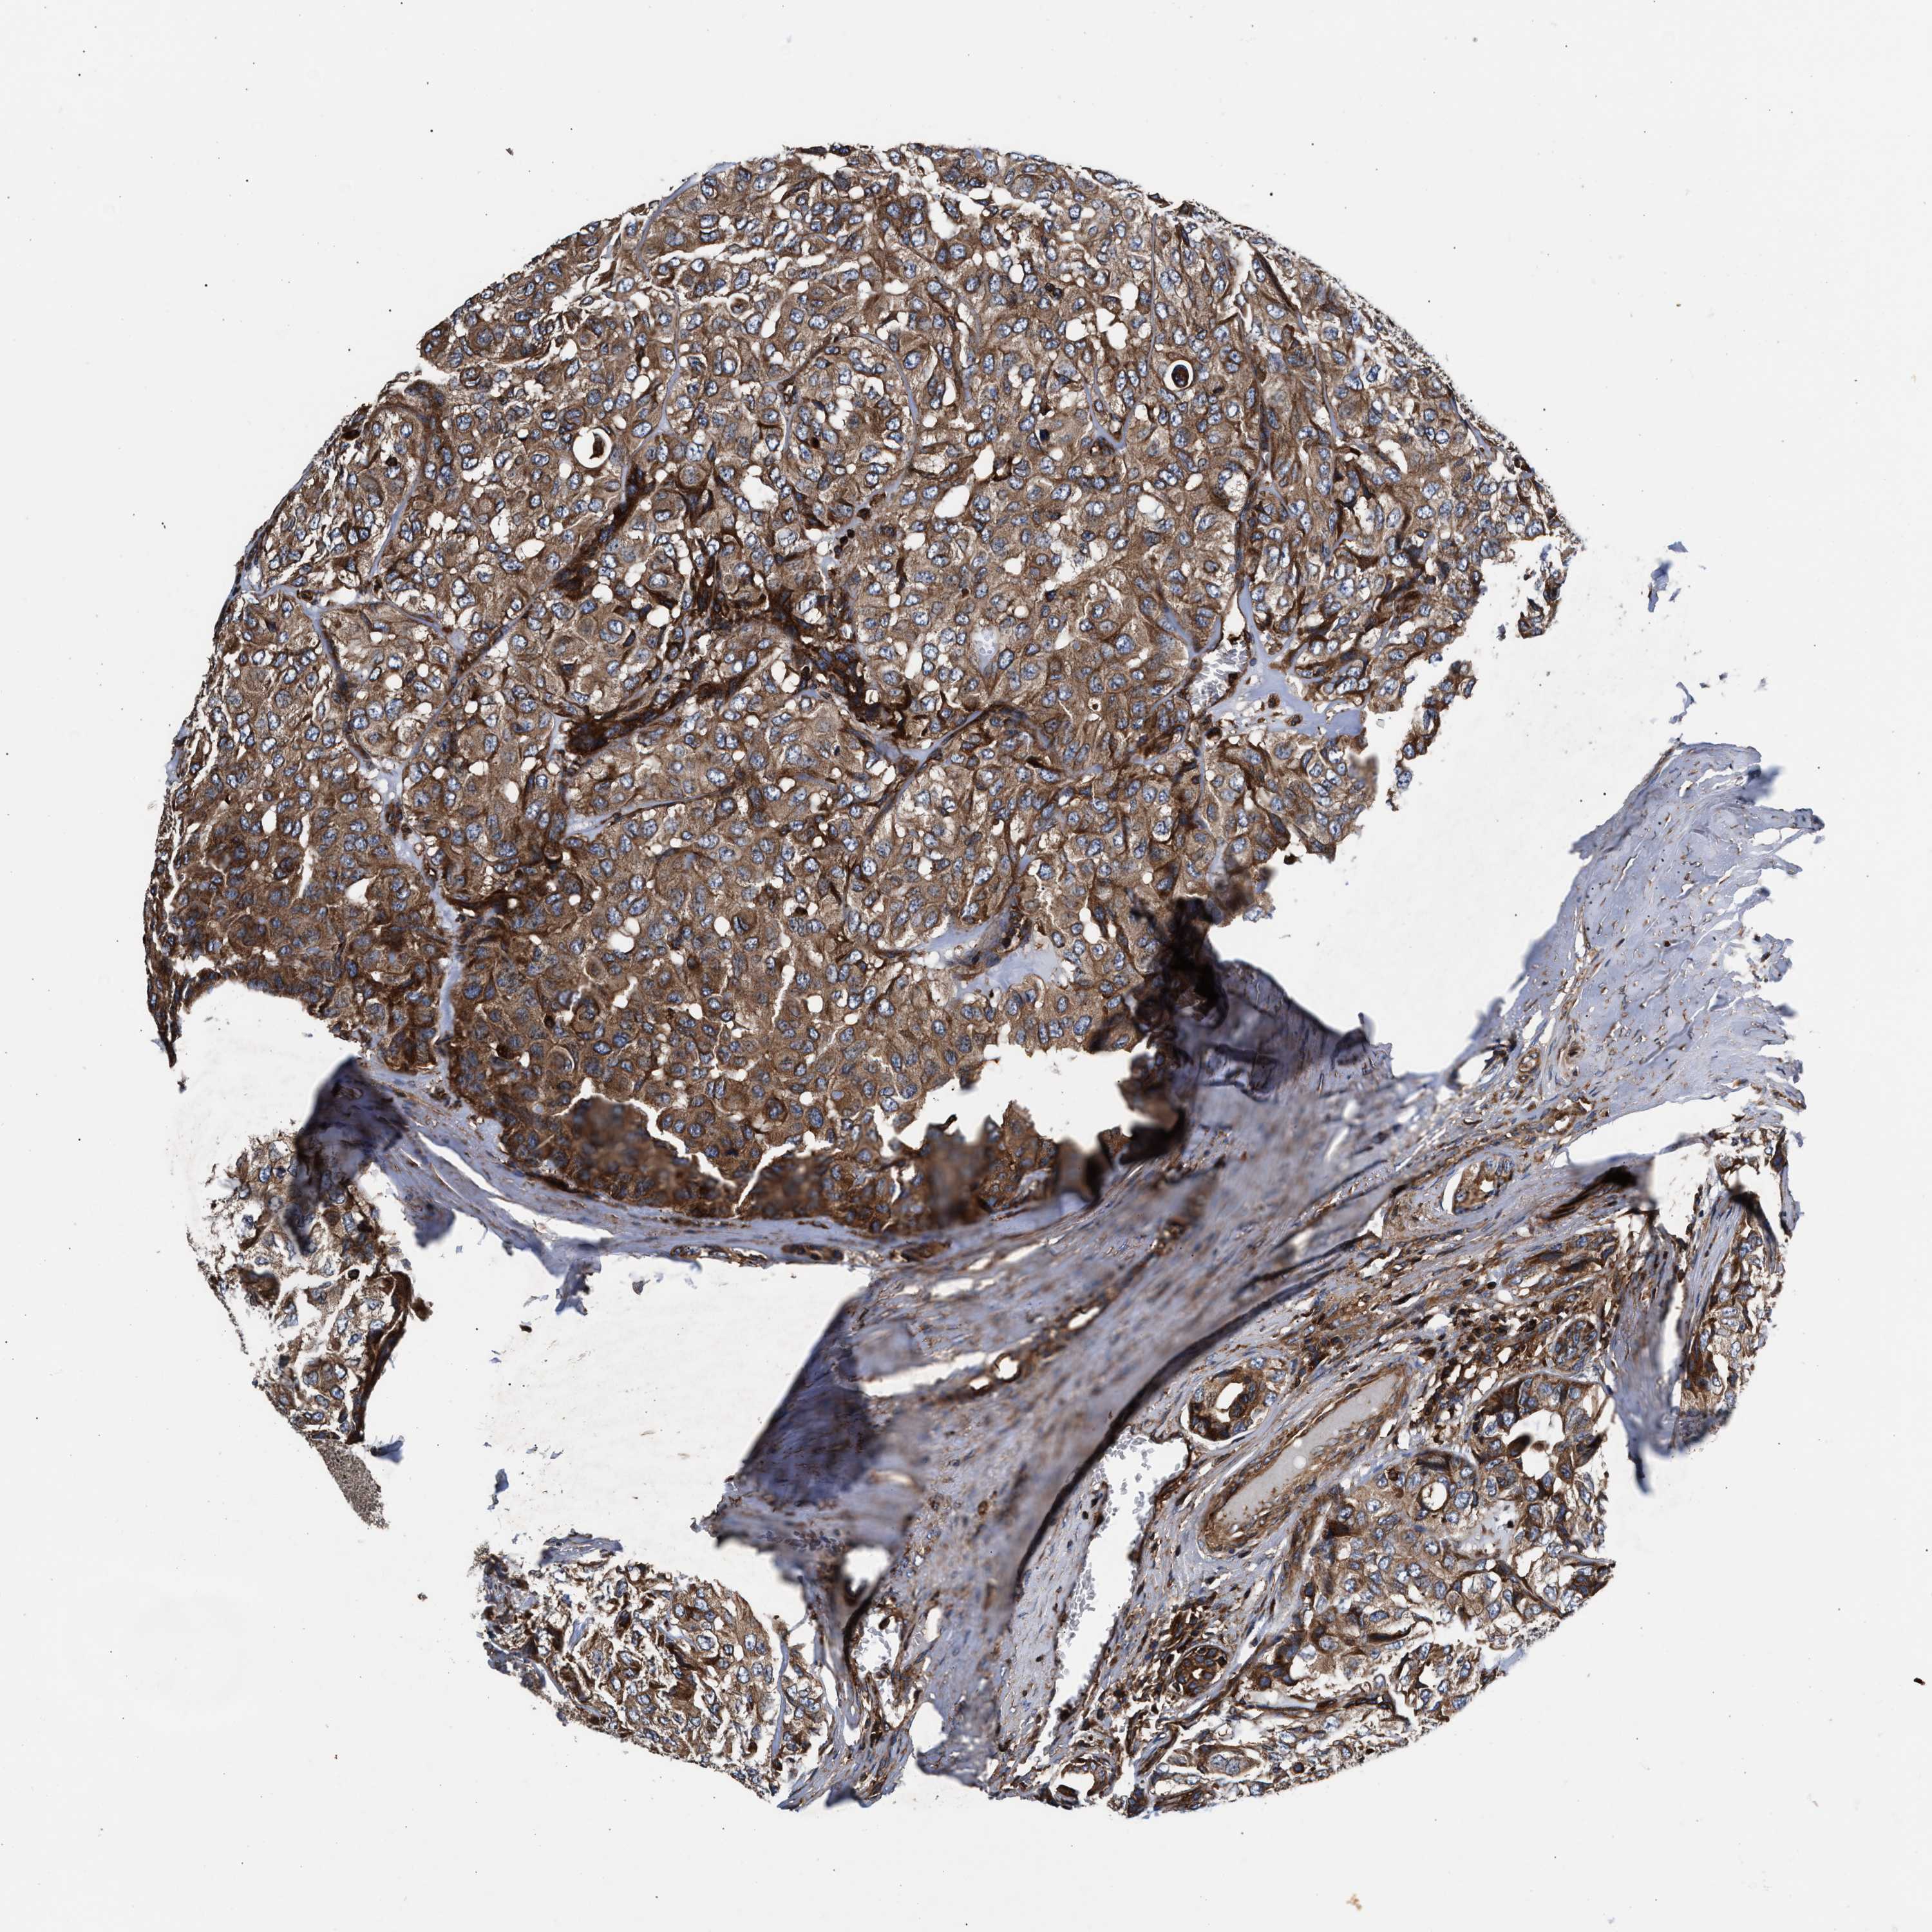

HEAD AND NECK CANCER - Protein expressioni

A mouse-over function shows sample information and annotation data. Click on an image to view it in a full screen mode. Samples can be filtered based on level of antibody staining by selecting one or several of the following categories: high, medium, low and not detected. The assay and annotation is described here.

Antibody stainingi

Antibody staining in the annotated cell types in the current human tissue is reported as not detected, low, medium, or high, based on conventional immunohistochemistry profiling in selected tissues. This score is based on the combination of the staining intensity and fraction of stained cells.

Each image is clickable and will lead to virtual microscopy that enables deeper exploration of all samples and also displays staining intensity scores, fraction scores and subcellular localization as well as patient and tissue information for each sample.

Antibody HPA021176

Antibody HPA021177

Antibody HPA027736

Staining

High

Medium

Low

Not detected

Intensity

Strong

Moderate

Weak

Negative

Quantity

>75%

75%-25%

<25%

None

Location

Nuclear

Cytoplasmic/membranous

Cytoplasmic/membranous,nuclear

Squamous cell carcinoma, NOS